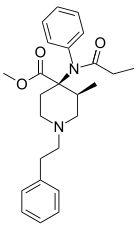

Anilidopiperidines

- 3-Allylfentanyl

- 3-Methylfentanyl

- 3-Methylthiofentanyl

- 4-Phenylfentanyl

- Alfentanil

- α-Methylacetylfentanyl

- α-Methylfentanyl

- α-Methylthiofentanyl

- Benzylfentanyl

- β-hydroxyfentanyl

- β-hydroxythiofentanyl

- β-Methylfentanyl

- Brifentanil

- Butyrfentanyl

- Carfentanil

- Fentanyl

- Lofentanil

- N-Methylcarfentanil

- Mirfentanil

- Ocfentanil

- Ohmefentanyl

- Parafluorofentanyl

- Phenaridine

- R-30490

- Remifentanil

- Sufentanil

- Thenylfentanyl

- Thiofentanyl

- Trefentanil

Structures